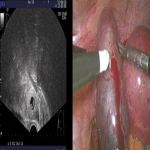

随着社会的发展进步,政府放开二胎政策。人工助孕技术增加的同时,宫外孕的病发率也大大的提高。宫外孕(异位妊娠)是指妊娠囊着床于子宫腔以外的其他位置,90%的宫外孕属于输卵管妊娠。孕早期可以通过全景四维彩超和动态血HCG排查!